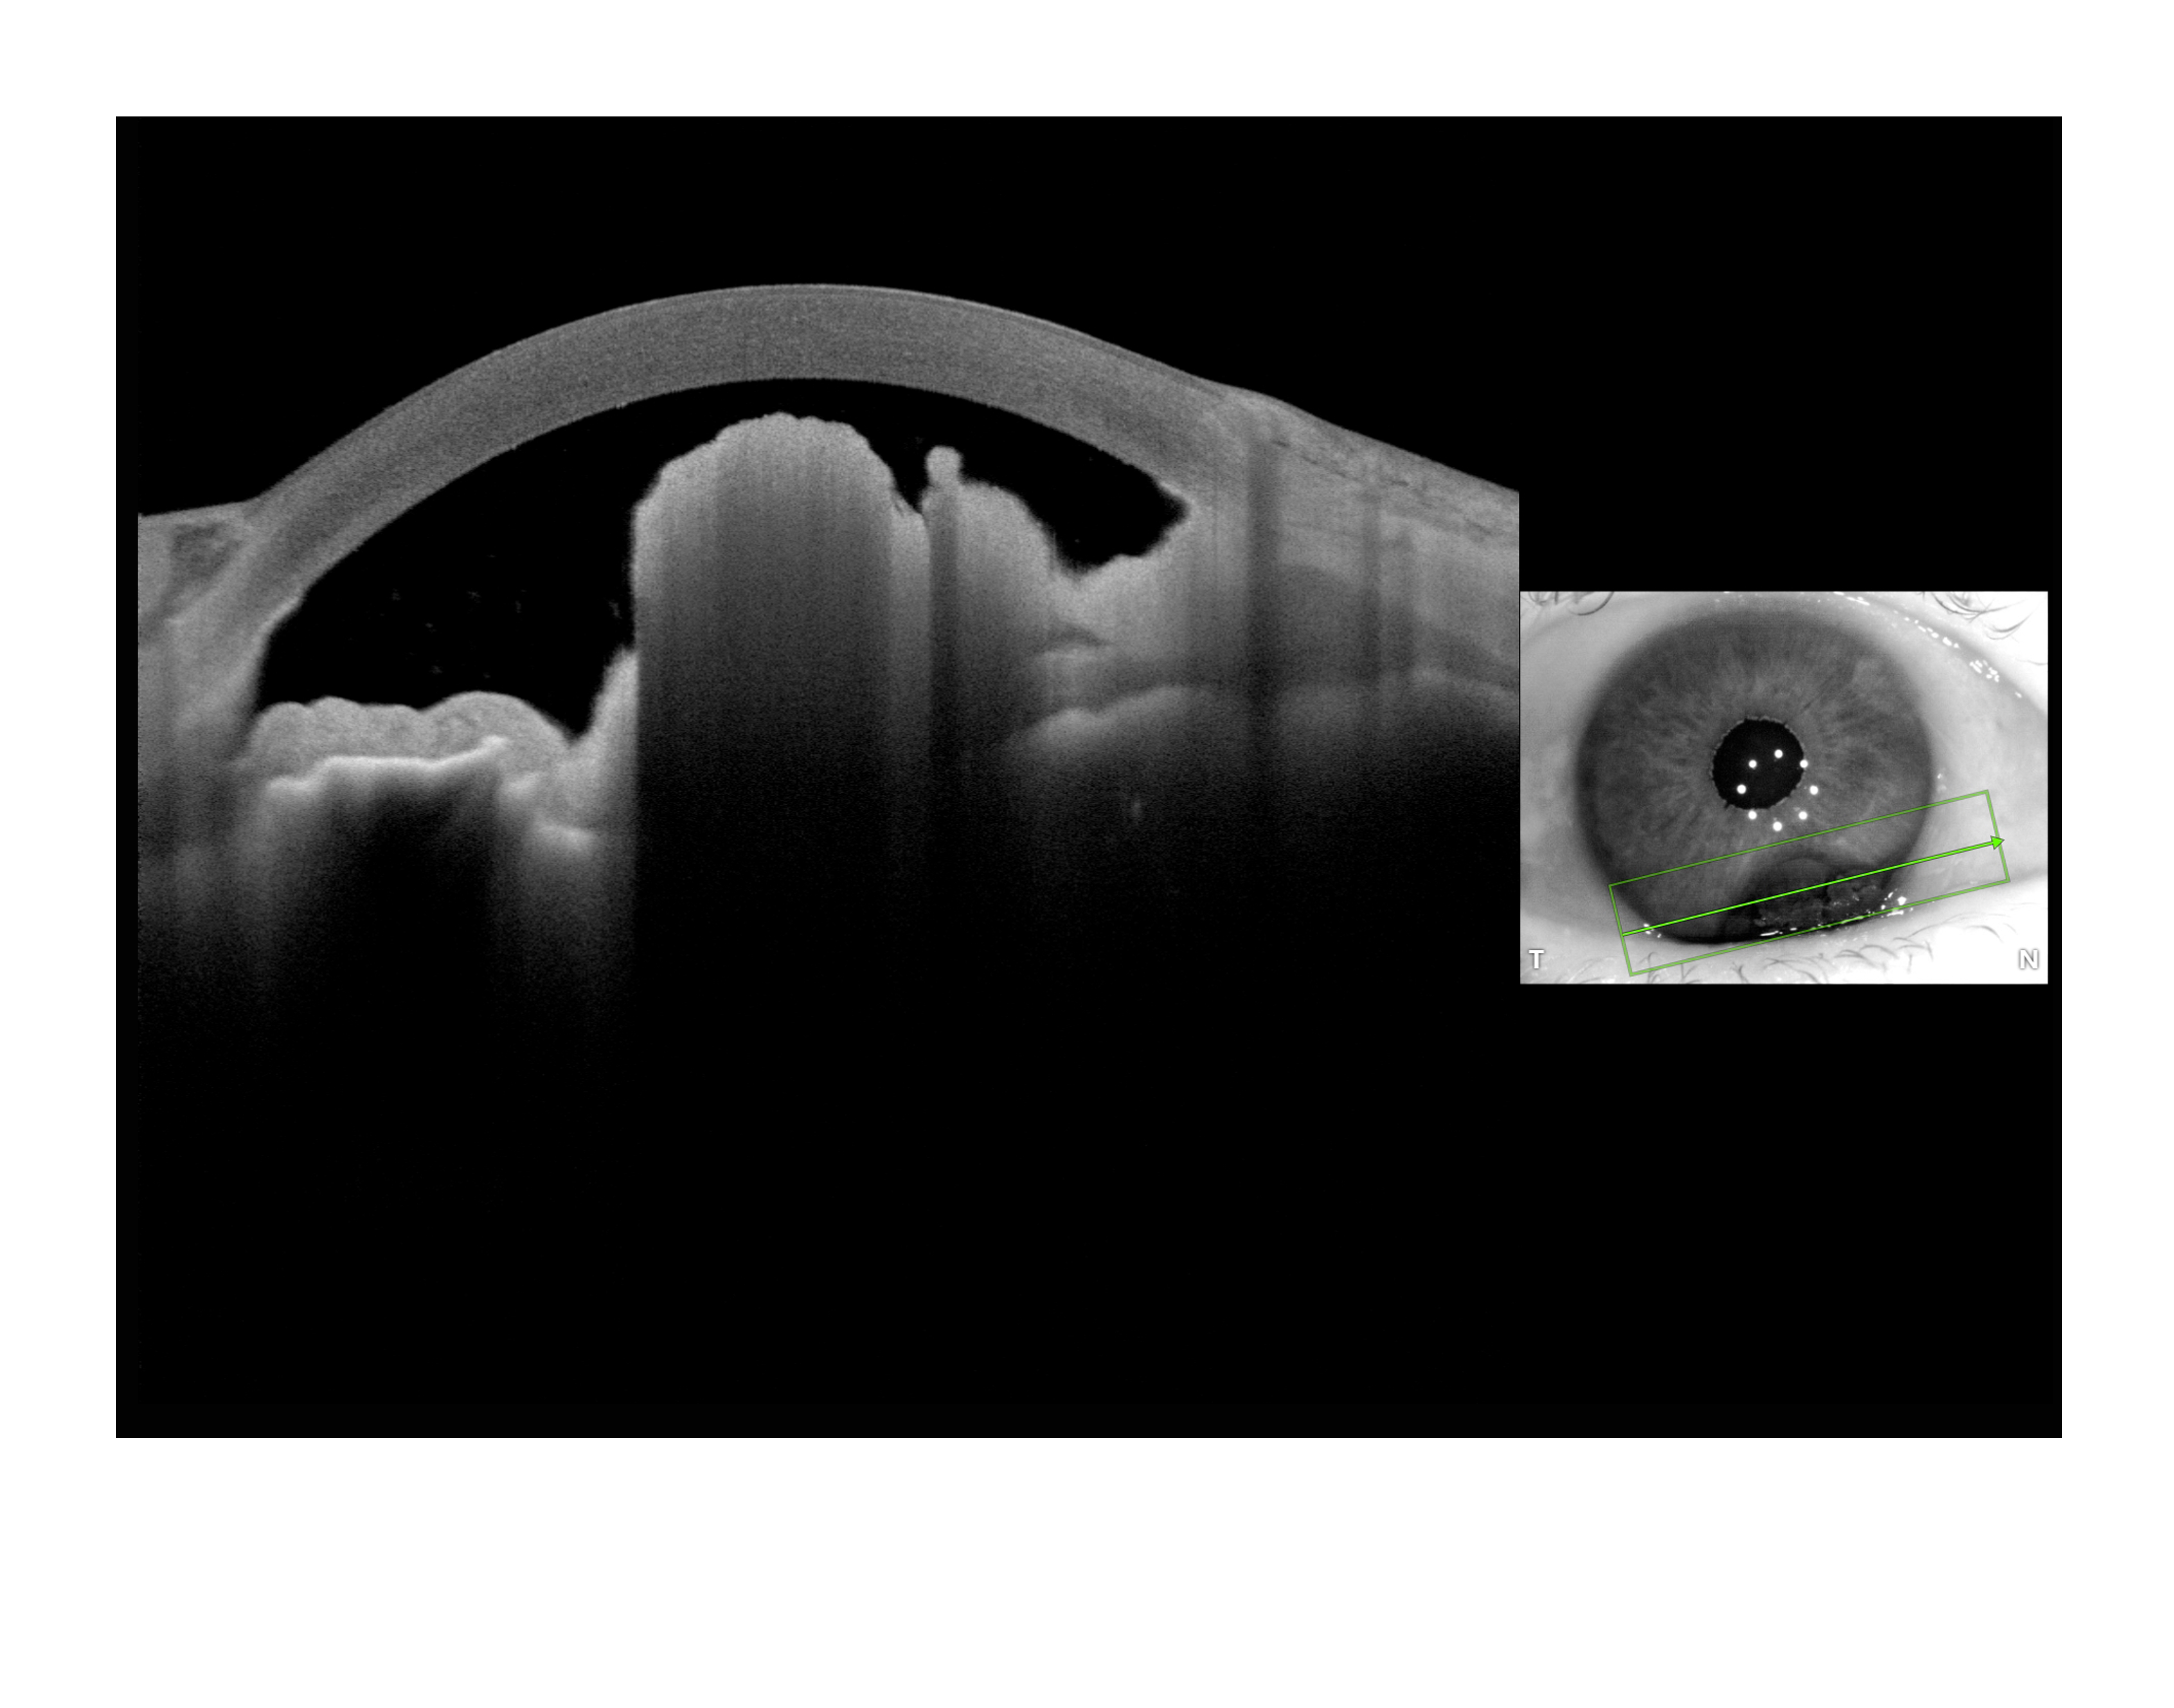

Anterion Melanoma Presented by Paul Crown, CRA, OCT-C This photograph received Third Place in the category "Optical Coherence Tomography" and was displayed in the 2024 OPS Exhibit. Filed Under Retina OPS Photo